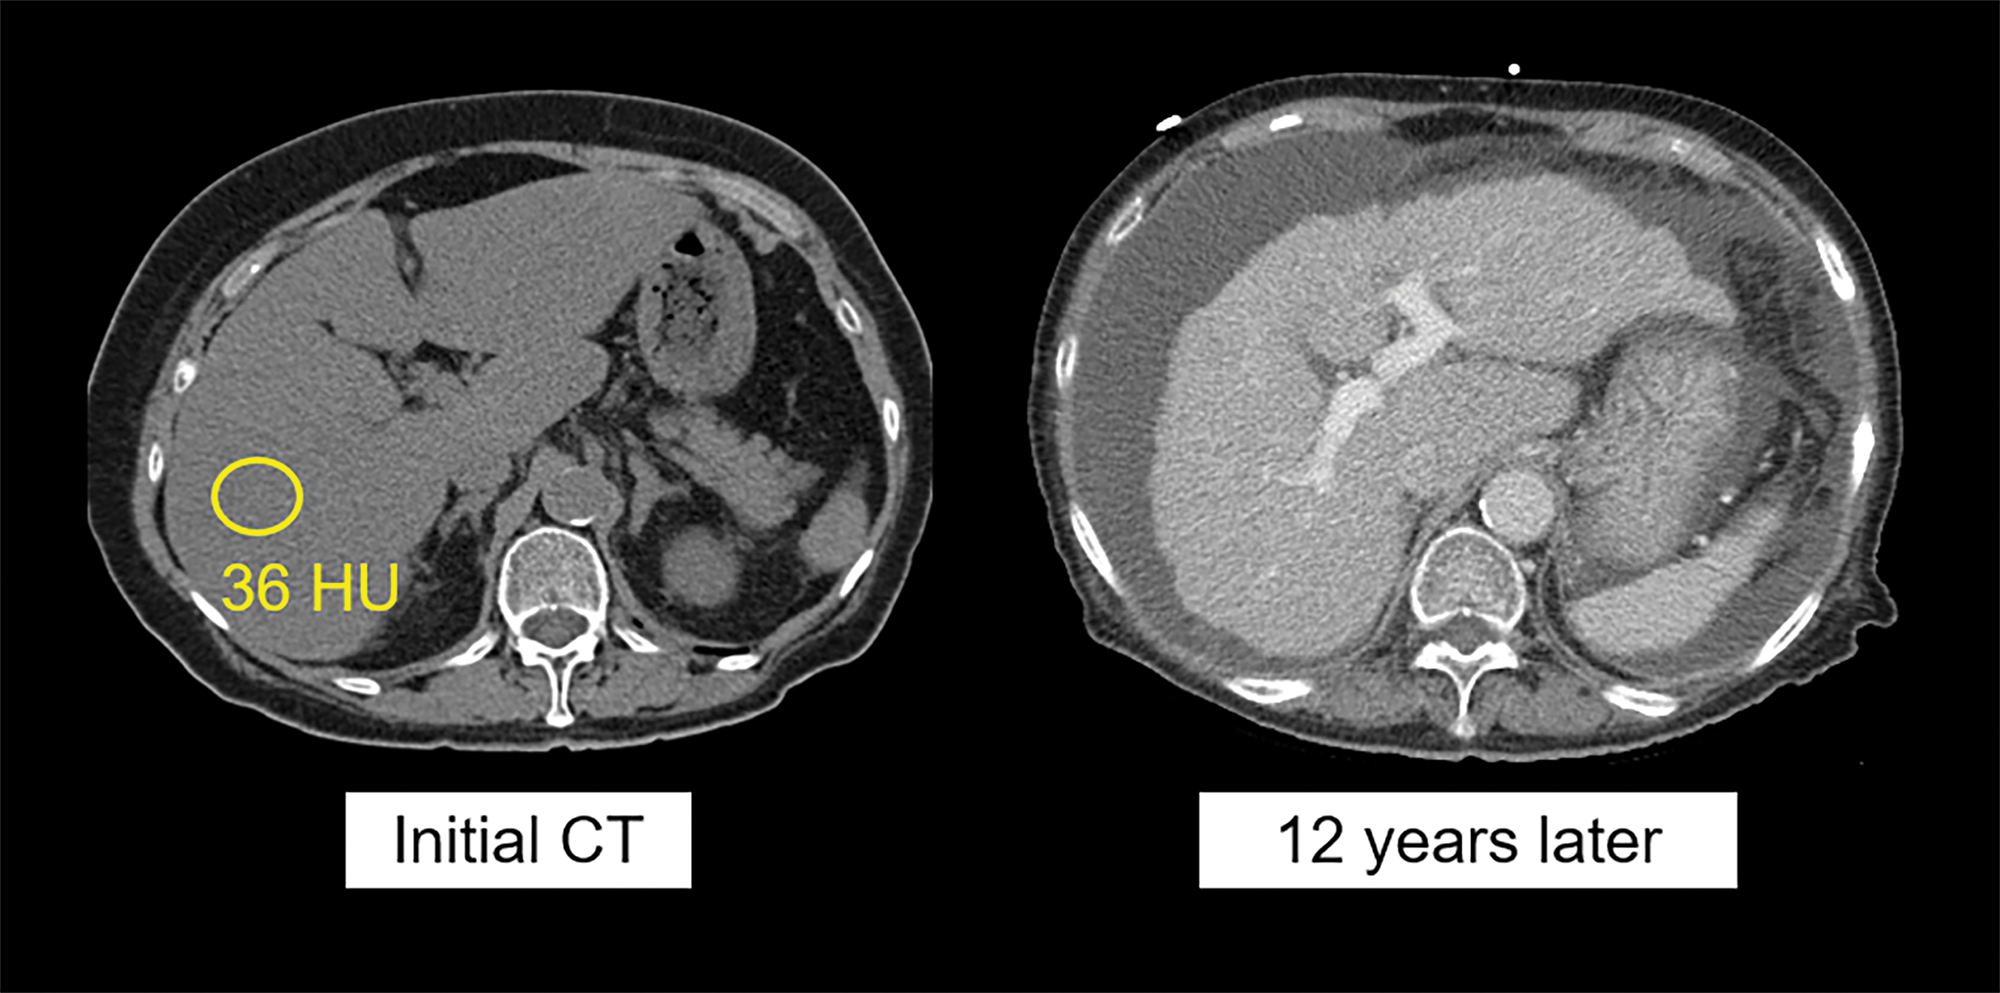

Non‑contrast CT image (left) in a 76‑year‑old woman shows moderate hepatic steatosis (36 HU, corresponding to 17% MR‑PDFF), as well as some degree of segmental redistribution and fissural widening, indicating likely fibrosis. Contrast‑enhanced CT (right) performed 12 years later demonstrates advanced cirrhosis and portal hypertension with obvious surface nodularity and ascites. The patient died of end‑stage liver disease within a year of the latter scan.